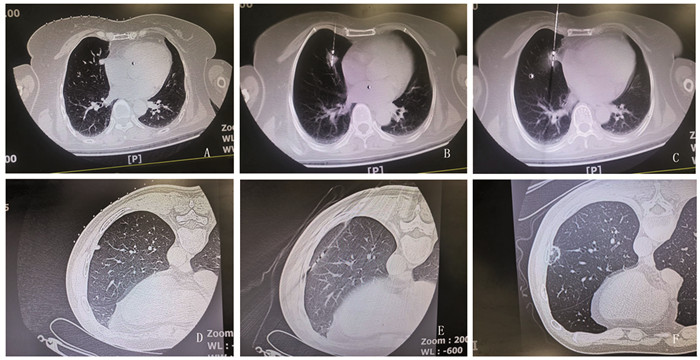

当针尖指向结节时,向前推送针体(进针),即调针、进针序贯进行(序贯穿刺模式)。随后,CT扫描核实结节与针尖位置,如果针尖方向偏离肺结节,则再次调整丝线的牵拉方向和张力,当针尖指向结节后,向前推送针体,直至针尖插入结节中心部位,启动消融过程,见图 2。本操作由两位有18年肺穿刺经验的医师独立完成。

![]() 图 2 微波针穿刺肺结节CT示意图Figure 2 CT operation diagram of using microwave needle in puncturing pulmonary nodulesA: the mediastinal subpleural nodule of middle lobe of the right lung is 1.0 cm in length; B: the tip of the ablation needle was inserted into the pulmonary nodules, and the nodules were radially adjusted to remove 1 cm from the pleura to initiate ablation; C: euring nodular ablation, needle tip slip occurred due to cough, and the tip moved 1 cm forward beyond the anterior edge of the nodules; D: the subpleural nodule of lower lobe of the right lung has a diameter of 0.5 cm; E: needle tip pushing nodules forward 2.5 cm; F: CT reexamination 2 days after ablation; A-C: an 87-year-old female with mediastinal subpleural lung adenocarcinoma in middle lobe of the right lung; D-F: a 59-year-old man with subpleural metastases in inferior lobe of the left lung 4 years after nephrectomy of renal carcinoma.

图 2 微波针穿刺肺结节CT示意图Figure 2 CT operation diagram of using microwave needle in puncturing pulmonary nodulesA: the mediastinal subpleural nodule of middle lobe of the right lung is 1.0 cm in length; B: the tip of the ablation needle was inserted into the pulmonary nodules, and the nodules were radially adjusted to remove 1 cm from the pleura to initiate ablation; C: euring nodular ablation, needle tip slip occurred due to cough, and the tip moved 1 cm forward beyond the anterior edge of the nodules; D: the subpleural nodule of lower lobe of the right lung has a diameter of 0.5 cm; E: needle tip pushing nodules forward 2.5 cm; F: CT reexamination 2 days after ablation; A-C: an 87-year-old female with mediastinal subpleural lung adenocarcinoma in middle lobe of the right lung; D-F: a 59-year-old man with subpleural metastases in inferior lobe of the left lung 4 years after nephrectomy of renal carcinoma.1.4 观察内容

本研究消融针穿刺成功101例(94.4%),显示挂线法辅助穿刺具有较高成功率。当针尖距离结节≤0.5 cm时,应精细调针,谨慎进针。尤其针尖插入结节表层并偏离中心区域时,对于mGGN和pGGN仍可尝试结节内调针,将针尖插入结节中心区域。反之部分sPN结节内调针困难,常需退针到结节边缘,重新调整针向、进针;胸膜下结节宜采用与胸膜切线平行路径进针,尽可能肺内调针距离≥2 cm,此时消融针与胸壁夹角可能很小,宜采用支架辅助挂线法调整针向(图 1D、图 2D~E);当肺结节前缘或侧缘毗邻胸膜、血管等重要结构时,先将针尖插入结节中心,采用挂线法径向拨动结节脱离前缘或侧壁重要结构,随后针尖贯穿结节,保持丝线张力和安全距离后,启动消融过程(图 2A~C)。针尖径向调针是实现结节精准穿刺的重要方法(图 2A~B),调针距离受多种因素影响:如针杆硬度、长度、胸壁及肺内走行距离、针尾受力大小、肋间隙宽度、针杆与肋骨上下缘距离、基础肺疾病和针尖肺内部位等。穿刺失败6例(5.6%),失败原因与胸壁厚、结节小、磨玻璃样结节、毗邻胸膜或膈肌结节、呼吸幅度大以及针尖推顶、针体滑脱和掩蔽现象有关。其中退针2例,针尖插入肺结节非中心区域4例(3环靶区中、外2/3区域)。